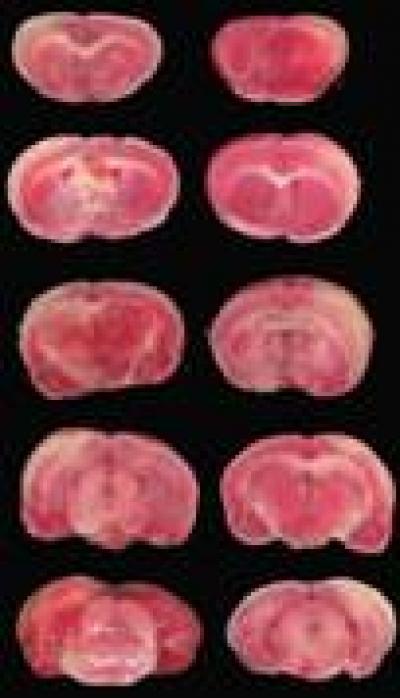

This image shows acupuncture at Neiguan (PC6) with a lifting and thrusting frequency of 3 Hz and long duration of 60 seconds could significantly reduce cerebral infarction in rat models of middle cerebral artery occlusion.

The individual difference and non-repeatability in acupuncture have not only restricted the development of acupuncture, but have also affected the specificity of acupoints. As reported in a recent study published in the Neural Regeneration Research (Vol. 8, No. 28, 2013), acupuncture at Neiguan (PC6) was performed using a custom lifting- and thrusting-controlled machine. A frequency of 1, 2, or 3 Hz and duration of 5, 60, or 180 seconds were used to observe cerebral blood flow and ratio of infarct volume recovery. An orthogonal design was used to sift the optimal parameter of Neiguan acupuncture. Experimental results showed that stimulation at Neiguan with a frequency of 1 Hz and long duration of 180 seconds or 2/3 Hz and long duration of 5/60 seconds significantly increased cerebral blood flow and decreased the ratio of infarct volume.